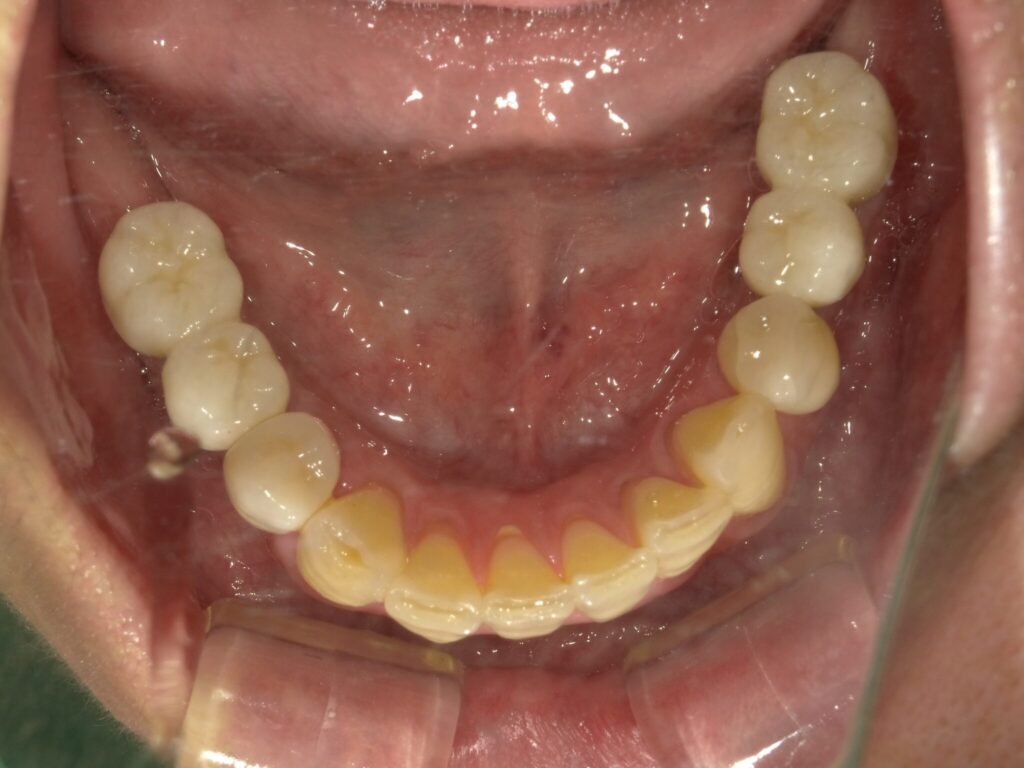

全顎治療症例

| 主訴 | 全体的に見た目を綺麗にしたい。奥歯でしっかり噛みたい。 |

| 診断名・ 主な症状 |

臼歯部欠損 |

| 治療内容 | インプラント埋入(左下5・6,右下5・6,左上4・6) サイナスリフト(左上4・6) ジルコニアBr(右上6−左上3) E –MAX CAD(右下4) セラミックインレー(左下4) |